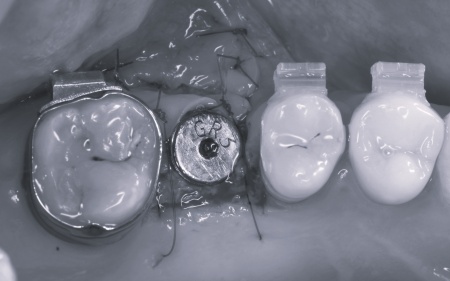

矯正がある程度進んだ段階で、右上と左下のインプラント手術を実施しました。

その際、右上の奥歯は鼻の奥にある空洞(上顎洞)に近く骨の厚みが不足していたため、上顎洞の粘膜を押し上げた部分に人工骨を入れて骨を増やすソケットリフトを併用しています。

一方、左下の奥歯は頬側(外側)の骨が薄かったため人工骨を入れて骨量を補うGBR(骨再生誘導法)を施しました。